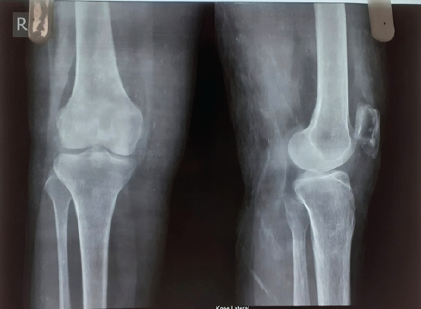

At the 6-week follow-up, the patient reported a marked reduction in pain and improved knee function. Physical examination showed no signs of recurrence, and the surgical site was healing well. Radiographs confirmed the absence of residual lesion (Fig. 6) [Table 1].

Figure 6: Post-operative X-ray.